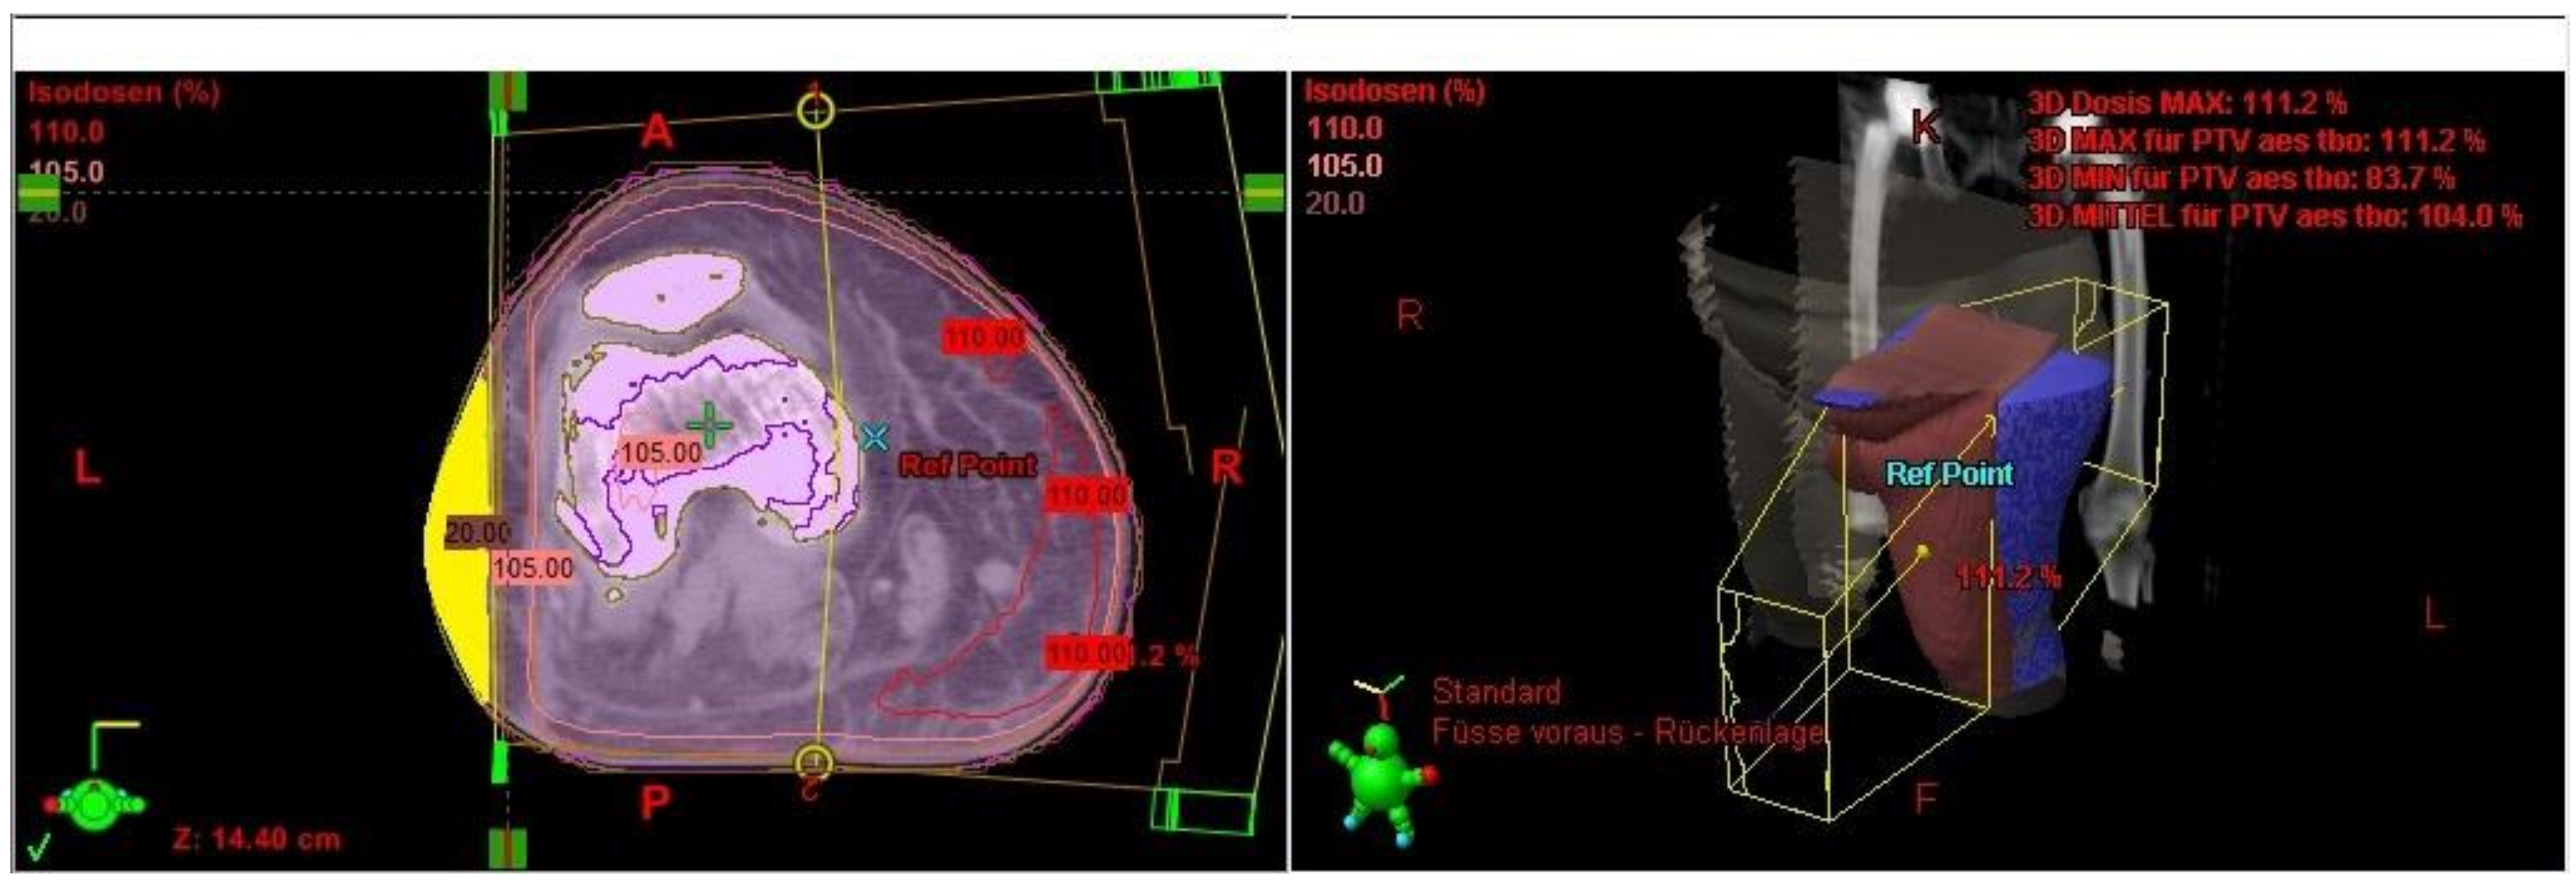

The irradiated part of the extremity was demonstrated in the radiation plan including the isodose lines to confirm a continuous lymph-sparing volume outside the 20% isodose level. If a boost was applied, the plan sum was considered. Depending on the extent of the radiation field, the extremity was defined from the middle of the ankle joint up to the hip joint or from the radioulnar joint up to the shoulder joint, respectively. The extremity and the continuous lymph-sparing volume were created as a 3D structure in the planning CT. In a few parts of the extremity the lymph-sparing volume was narrower due to anatomical and disease-specific reasons (Figure 1 and Figure 2). Bone volume was subtracted from the extremity volume (Figure 3 and Figure 4). The narrowest 10 cm of the lymph-sparing volume was also defined as a 3D structure (Figure 5).

Figure 2.

Relatively narrow part of the lymph-sparing volume (yellow) outside the 20% isodose line.